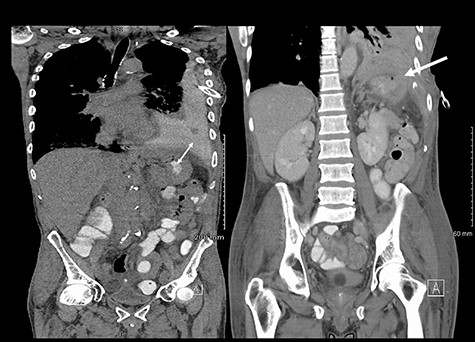

He maintained a high daily chest drain output of between 2.5 and 5 l. Upon recommencement of enteral feeding on day 3, we noticed an increase in opacity of the drainage fluid (Fig. 3). Normal triglyceride and chylomicron levels ruled out a chylothorax. Cultures from the drain eventually grew Enterococcus faecium, Candida albicans and Escherichia coli consistent with gut flora. At this point, an aerodigestive fistula was suspected. This was confirmed by a dye test subsequently performed with green ice cream, which tainted the drainage fluid green (Fig. 4). A repeat CT scan with oral and intravenous contrast delineated a fistula between the greater curvature of the stomach and the left basal pleura, with an extensive empyema (Fig. 5).

(Left) Contrast in stomach and pleural fluid are iso-dense confirming a fistula; (Right) neck of hernia in the diaphragm.

There are no specific signs of GPF on a plain film. Surrogate signs of a diaphragmatic defect include an intrathoracic stomach or nasogastric tube and elevation of the hemidiaphragm [5]. Notably, up to 66% of diaphragmatic injuries are missed on a plain film [5]. Although CT has a specificity of up to 99% for diagnosing diaphragmatic defects [5], it is again not specific for GPFs. Based on our institutional experience, the diagnostic yield for a GPF can be increased with modifications to CT protocols. The administration of both oral and intravenous contrast allowed visualisation of contrast extravasation from the stomach into the pleural cavity. Clamping of the chest drain and keeping the patient supine for an hour after consumption of oral contrast ensured that there was maximal accumulation of contrast in the pleural cavity. The gold standard for diagnosis remains direct intra-operative visualisation [2].